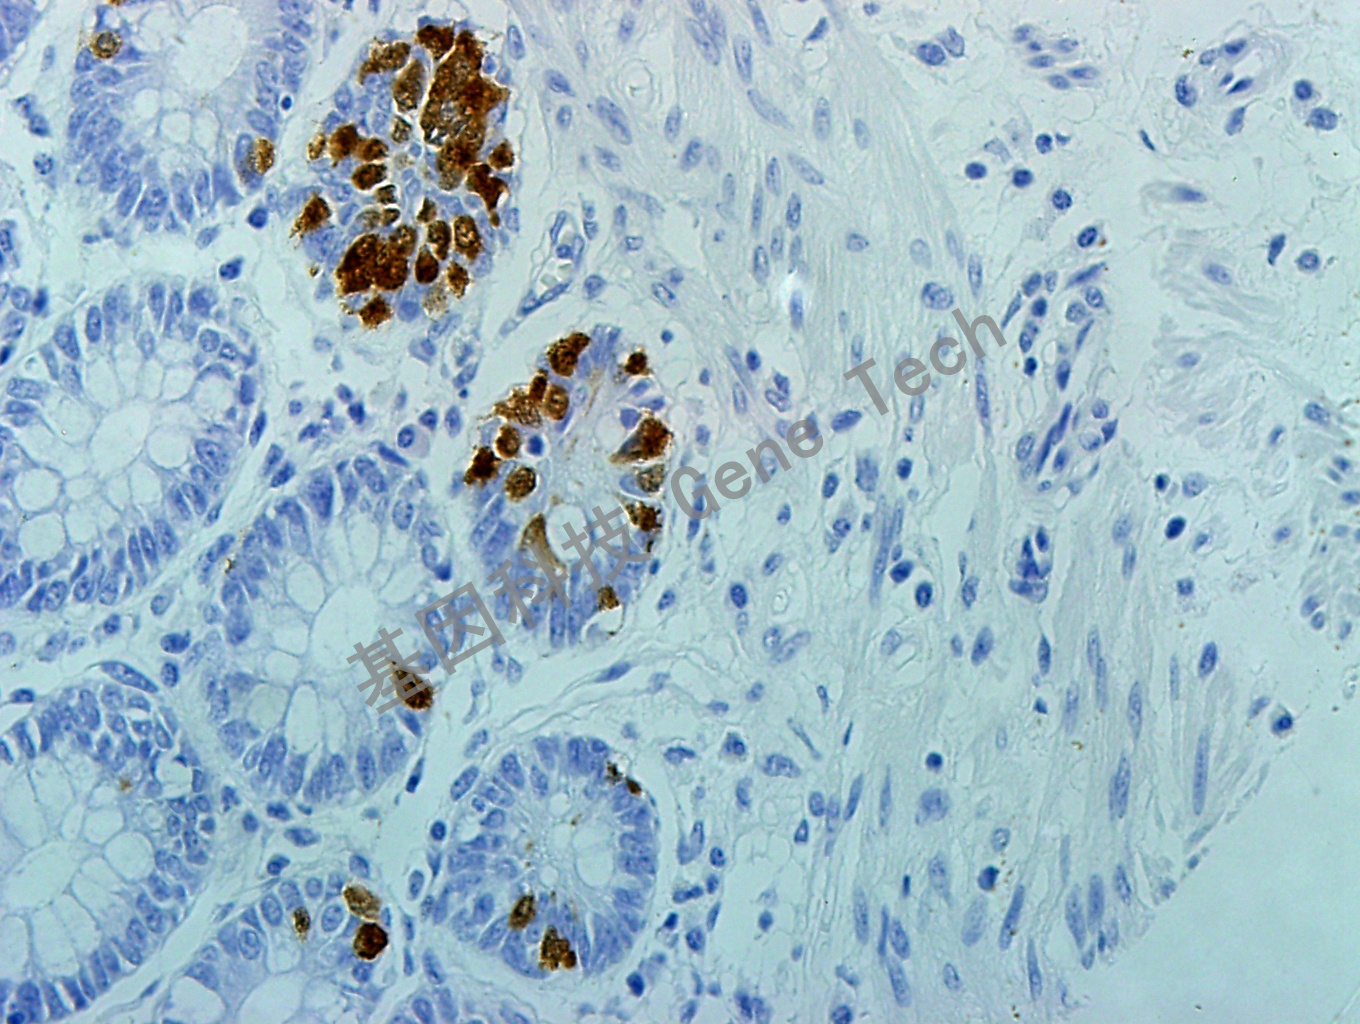

| 預處理:高pH熱修復 | 陽性部位:細胞漿 | 陽性對照:闌尾/結腸癌 |

| 結腸癌石蠟切片,用Serotonin(GT2337)染色,細胞漿陽性,DAB顯色 | ||